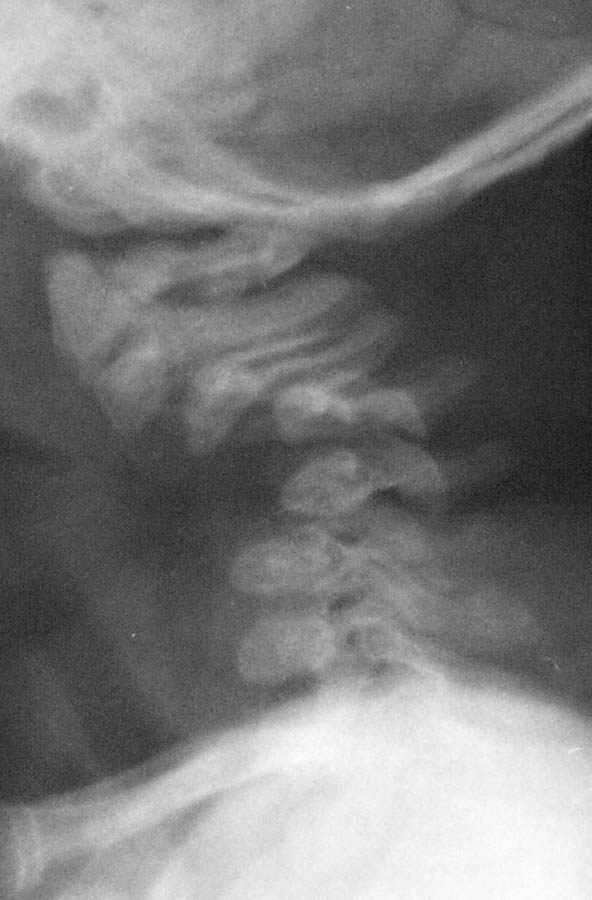

Девочка 5 месяцев, дочь коллеги, врача-анестезиолога, тетрапарез, в ногах спастический в руках - вялый, усугубившийся после "мануальной терапии".

Данные рентгена,КТ и МРТ прилагаются. Кроме того, имеется двухсторонний врожденный вывих бедра. По совокупности данных - болезнь Ларсена. В шейном отделе - дисплазия и гипоплазия суставных отростков С3-С5 с передним подвывихом и антелистезом, патологическим кифозом и стенозом позвоночного канала до 55% от исходного (5 мм при исходном 9 мм). Spina bifida occulta в 5 сегментах, в том числе расщепление задней дуги атланта, агенезия его передней дуги. Признаки спинальной компрессии и диффузной миелопатии на уровне стеноза. Вопрос - возможно ли в таком нежном возрасте оперативное лечение и вообще, какая должна быть тактика ?